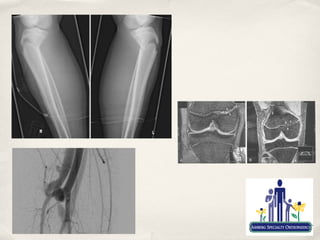

Fractures

✤   Becoming more common and more severe in children

✤   Greater level of sports participation

✤   High energy sports

✤   motorized sports

✤   High level contact sports

✤   MVAs and unbuckled children in SA!!

✤   Fracture related growth problems are seen most frequently after

injuries about the knee

✤   Can have life and limb threatening consequences

✤   Need to have a high index of suspicion in growing child

✤   Not a sprain/strain unless proven otherwise

✤   Should almost always get at least an xray in knee injured child

✤   Have a low threshold for advanced imaging

✤   Don’t normally recommend “stress views”

Salter-Harris classification

✤   Distal Femoral and Proximal Tibial Physeal fractures

✤   Most common fractures mistaken for ligament injury

✤   Need a high index of suspicion

✤   Treat as such until proven otherwise

✤   Can be most devastating to growth and life/limb

✤   Non-displaced fractures can usually be treated in a cast

✤   Displaced or intrarticular fractures frequently require

surgery